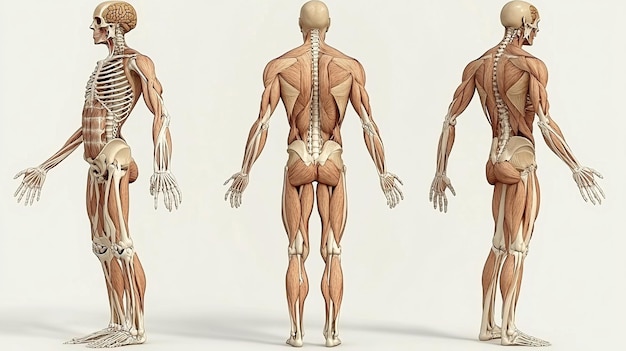

Human Anatomy Detailed 3D Model Of Male Muscular S 411059118

14/11/2025

ร่างกายมนุษย์